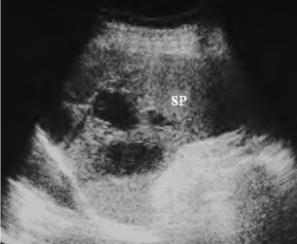

图24-5 外伤后脾破裂(实质内血肿)声像图

脾大,脾实质内见不规则无回声或低回声区。SP:脾脏